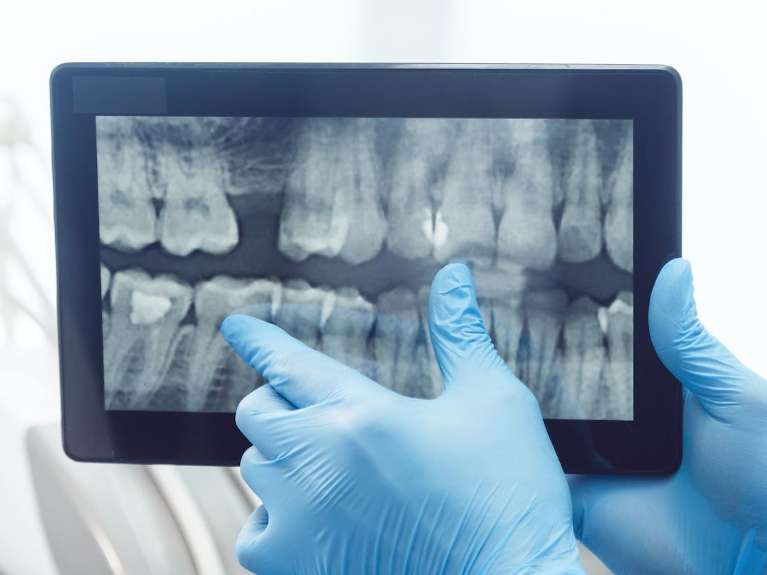

Digital X-Rays & Sensors

Using advanced electronic sensors and digital x-rays, we can capture detailed images of the oral cavity with significantly less radiation than traditional radiography. This technology allows for the immediate viewing of high-resolution images, aiding in accurate diagnoses and efficient treatment planning.

It's crucial for detecting cavities, monitoring bone loss, and evaluating the roots and nerves of teeth. For patients, this means quicker appointments and a deeper understanding of their oral health, as Dr. Klavy can share and discuss results on the spot.